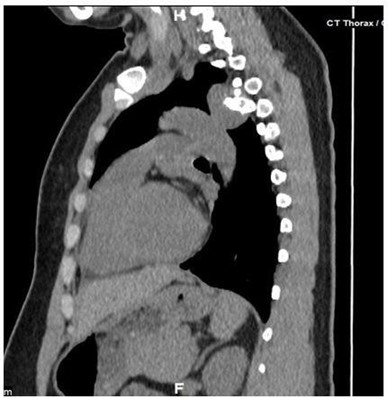

CECT scan was performed for better evaluation which showed a well defined lobulated hypodense mass lesion, lying in the left anterior paraspinal region at the level of the posterior end of the fourth rib. The lesion was arising from the posterior end of the left 4th rib. There were irregular nodular calcifications within it, and it measures ~3.1 (CC) x 2.6 (AP) x 2.5 (TR) cm. (Fig 2).

Figure 2. (A) CECT Thorax: Thin axial view showing a hypodense mass lesion arising from the posterior end of the 4th rib on the left side, irregular nodular seen calcifications within it. There is no obvious erosion of T4 vertebra. There is minimal enhancement in the mass lesion.

(B) Sagittal image showing the hypodense exophytic mass lesion in the posterior mediastinum.